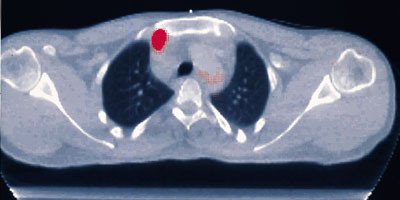

– PET har størst nytteverdi innen kreftdiagnostikken, og gir mulighet til å undersøke kroppen lokalt eller fra topp til tå. Det er særlig viktig å kunne påvise metastaser, lokalt tilbakefall eller gjenværende svulstvev hos pasienter der blodprøver og kreftmarkører gir mistanke om det, fremholder de to nukleærmedisinerne.

Foruten til påvisning av residiv eller spredning, er PET-undersøkelser verdifulle når man skal evaluere terapirespons, enten alene eller i kombinasjon med CT eller MR: – Her er det snakk om å spare pasientene for unødig behandling, alternativt sikre dem en mest mulig optimal behandling. Dette gjelder så å si ved alle kreftformer, opplyser Bogsrud.

Han sier flere nye studier viser at PET er kostnadseffektivt i behandlingen av lungekreft og tykktarmskreft, blant annet som følge av endret stadieinndeling. Dette medfører at noen pasienter får livreddende operasjoner, mens pasienter med metastaser kan spares for omfattende, nytteløse inngrep. I Frankrike har dette ført til at myndighetene har besluttet å bygge ut 50 PET-sentre, dvs. at dekningen blir én PET-skanner per million innbyggere, et tall som også blir regnet for å være den reelle behovsnormen. I USA er antall kliniske PET-undersøkelser mer enn fordoblet de siste 2–3 årene, i takt med at forsikringsselskapene har godkjent stadig nye indikasjoner.